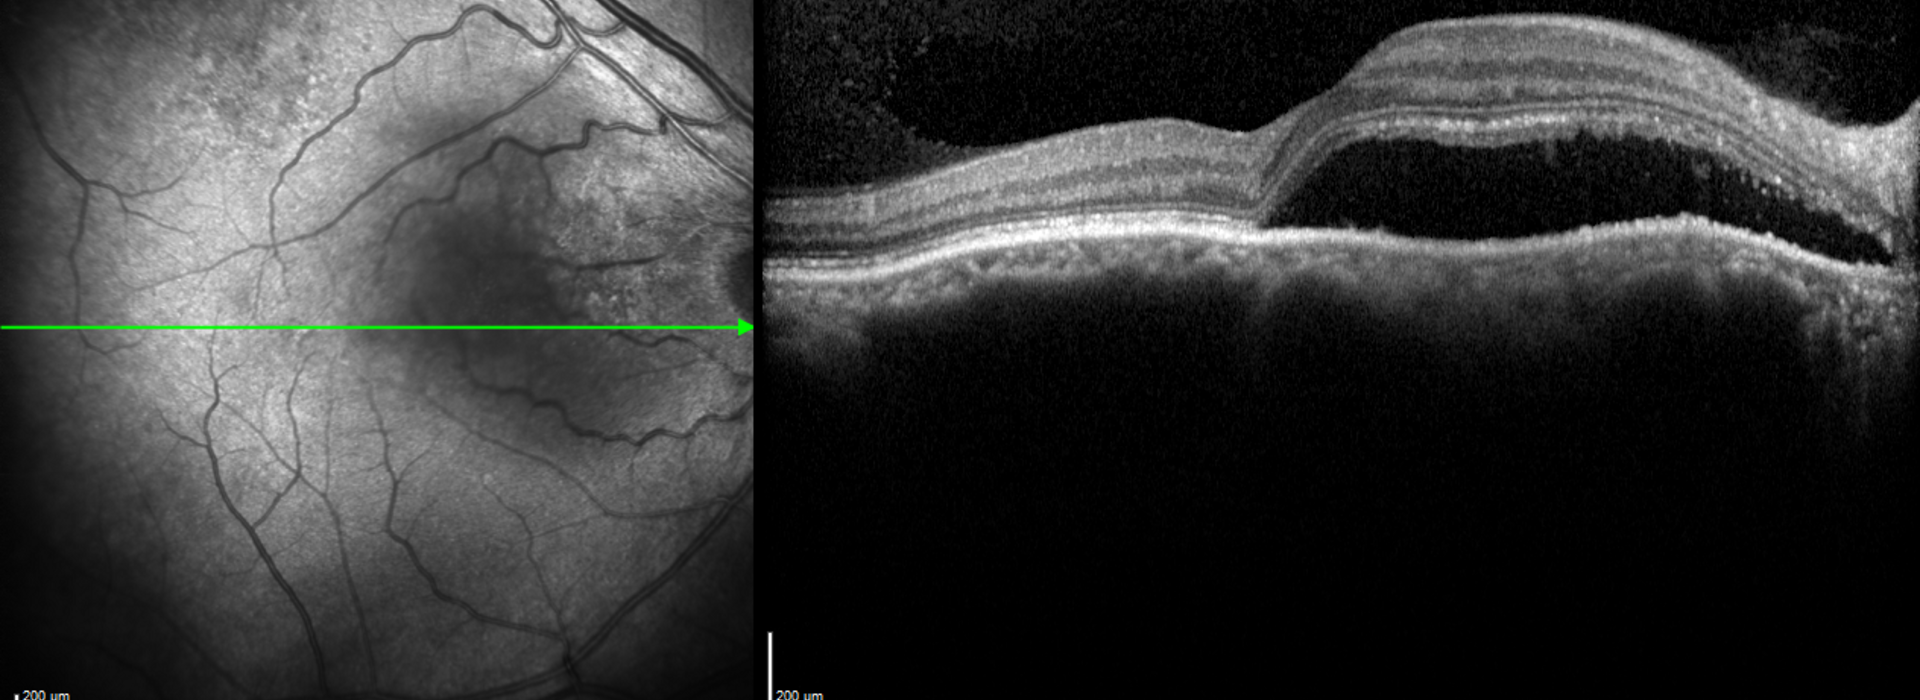

Clase 19 - Actualización de enfermedades paquicoroideas

OCT Summer Camp